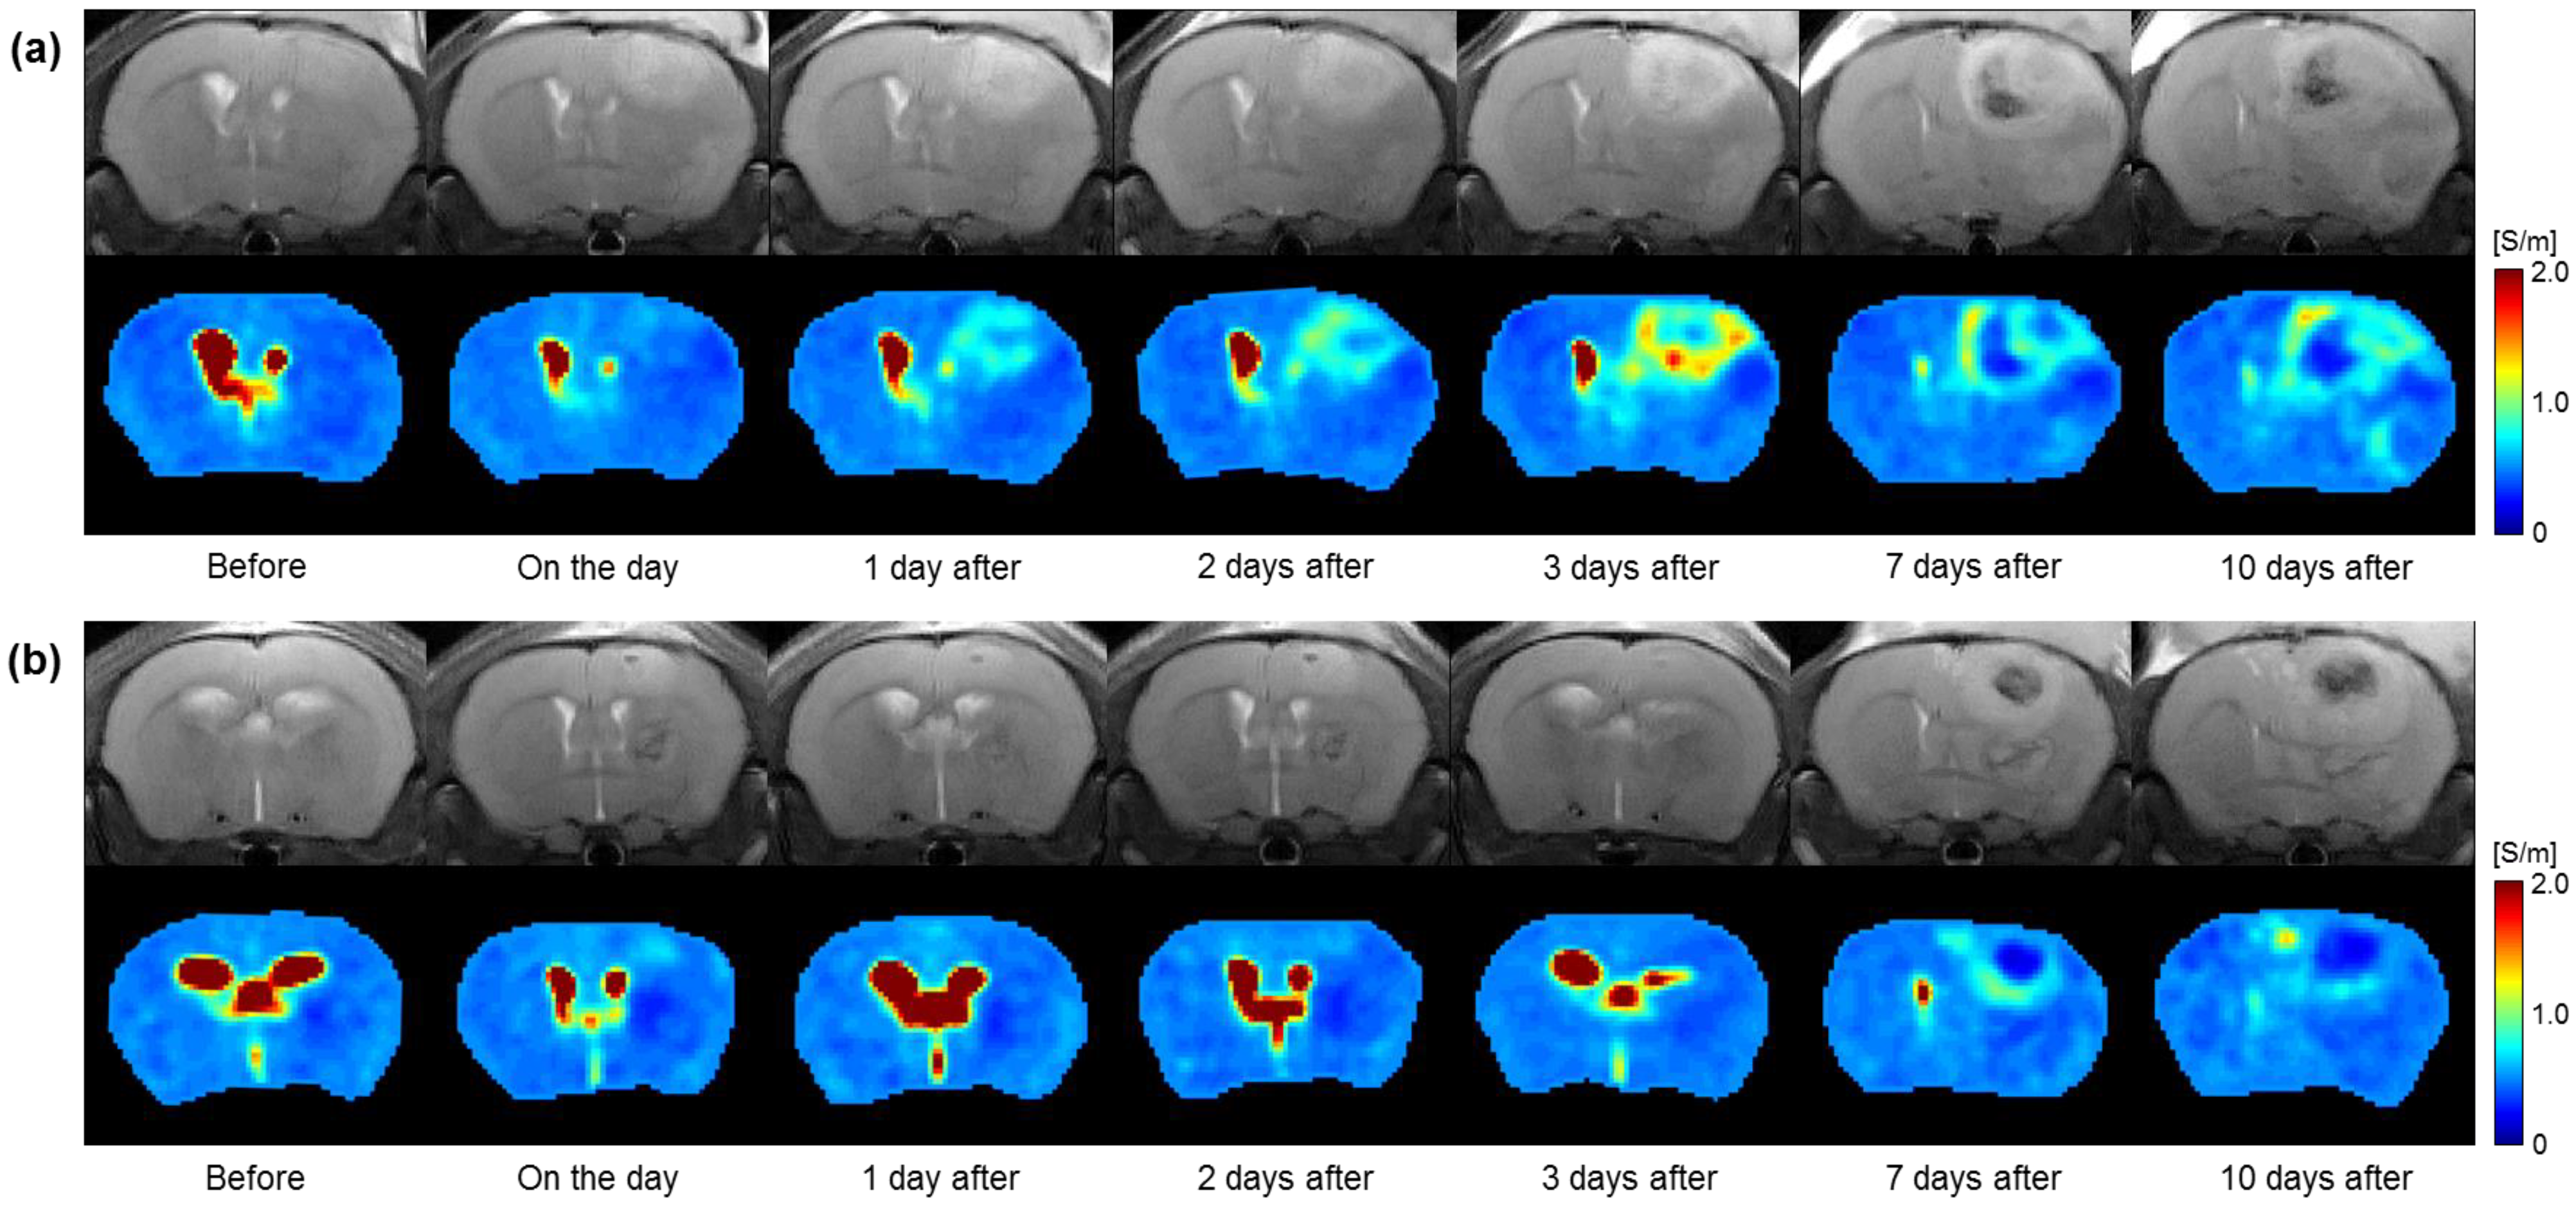

Figure 3 shows the full time-course images of the MR and electrical conductivity of the in vivo brain tumors with and without irradiation. All images were obtained before and 0, 1, 2, 3, 7, and 10 days after in the irradiated (Figure 3a) and non-irradiated (Figure 3b) groups. Compared to before irradiation, the morphological changes in the tumor region in the MR images show a similar pattern over time in both groups. However, the conductivity images show clear contrast changes between the two groups over time. Specifically, the conductivity of the irradiated group shows an increase up to 3 days after and a slight decrease up to 10 days. On the contrary, the conductivity of the non-irradiated group shows similar contrast up to 3 days and changes up to 10 days. The contrast of the tumor rims was clearly different between the two groups.

Figure 3. Time-course variations in MR (upper) and electrical conductivity (lower) images of in vivo mouse brains in the group with (a) and without (b) irradiation.